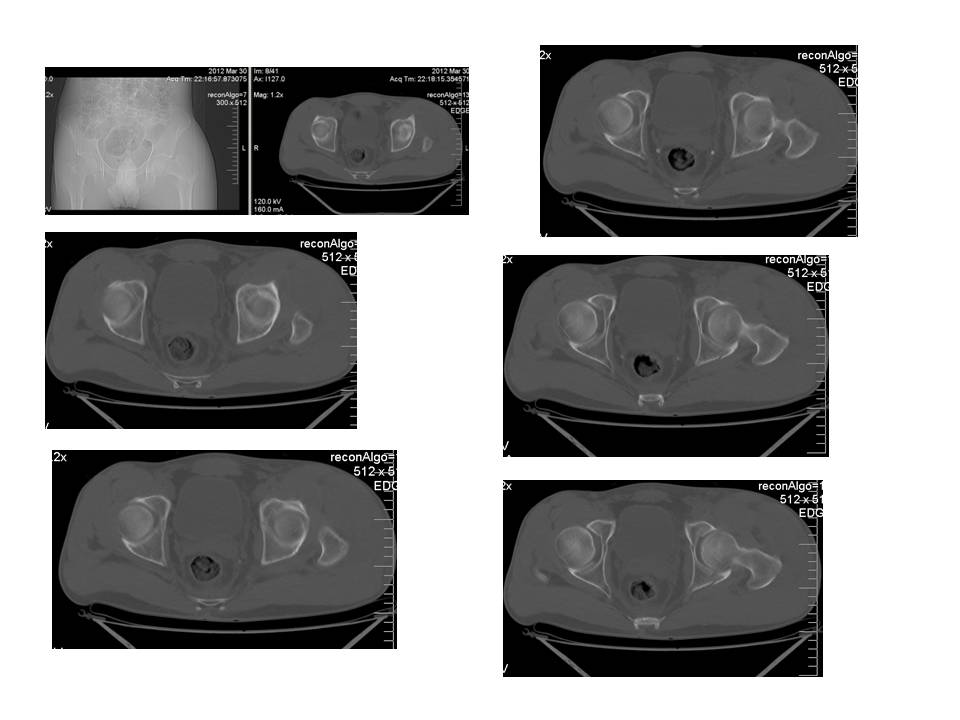

Больной 24 лет, травму получил катаясь на горных лыжах.

На рентгенограммах вертельный перелом. Но при детальном изучении

снимков появилось подозрение на перелом головки бедра. Это побудило

выполнить КТ.

На КТ перелом заднего края вертлужной впадины.

Планируем проксимальный стержень. А вот с вертлужной впадиной вопрос.

Синтезировать или консервативно.

"За операцию" внутрисуставной перелом, с вдавлением фрагмента

суставной поверхности.

"Против" смещенный фрагмент в задне-нижнем квадранте и в меньшей

степени нагружаем...